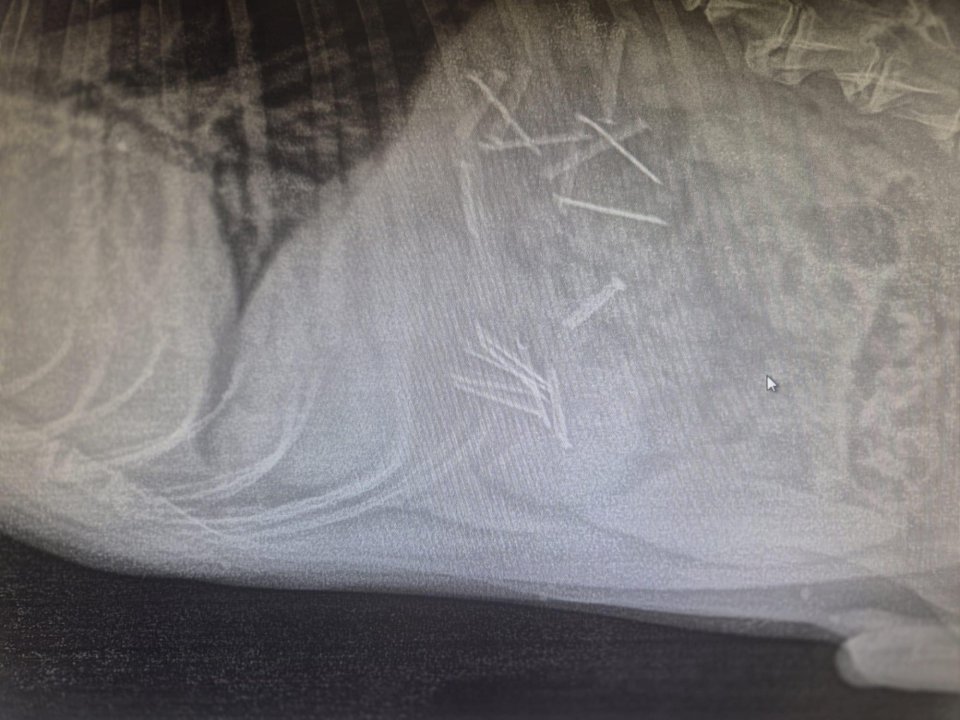

Okazało się, iż specjaliści usunęli z żołądka czworonoga aż 18 gwoździ.